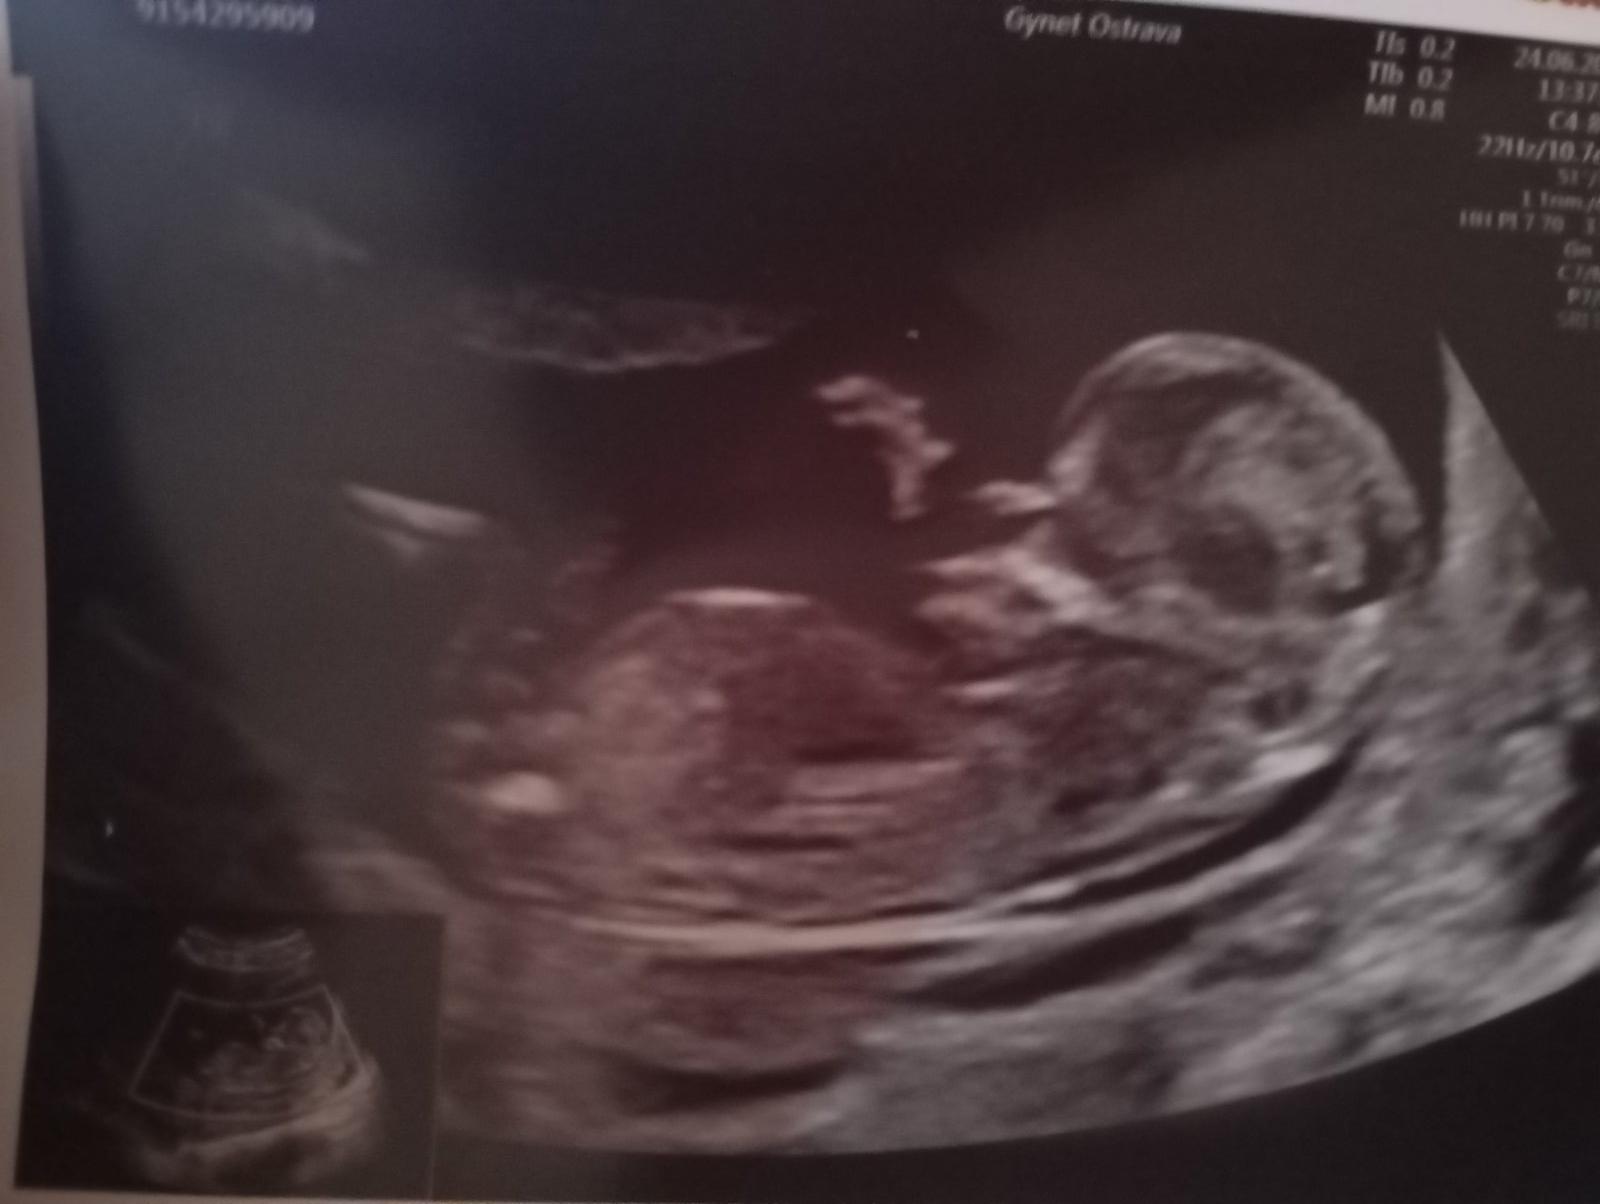

Nevolnosti, jsem mrzutá, akné a tep u kluků byl 140 tady mám 160. Řekl mi, že tipuje holku. Ale nemůže mi to říct na 100%. Nevím zda z toho to zjistíte? Prosím o radu :srdce:

@sarinka612 ahoj mě Dr řekl holka ..bříško mám úplně jiné než u kluků..a tep má 160 a kluci měli 140. Snad ano... cítím, že je to holčička. Snad to výjde. A jak to zvládáte???